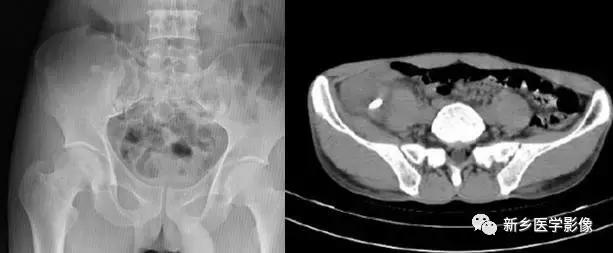

8、子宫平滑肌瘤(纤维瘤)

主要位于盆腔内,表现为不均一的点状钙化。